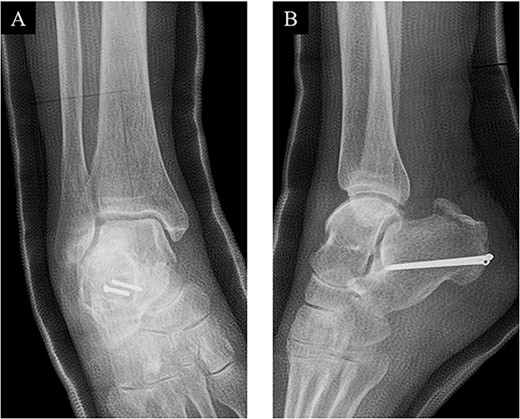

The surgery was performed under general anesthesia in the prone position with an air tourniquet and a fluoroscopy. First, an ~6 cm straight incision on the skin just above the calcaneal tuberosity was placed, and the fracture site was confirmed. After removing inclusions such as hematoma, the distal part of the Achilles tendon was sutured by the SLLS technique using USP 5 braided polyethylene and polyester suture thread (FiberWire; Arthrex Co., Naples, FL, USA) (Fig. 2A). Next, two 1.6-mm diameter ring pins (Tension Band Pin System; Acumed, Hillsboro, OR, USA) were parallelly inserted from the distal posterior part to the anterior part of the calcaneus body under a fluoroscopy (Fig. 2B). The bone fragment was anatomically reduced by pulling both of the suture ends, and the suture ends were passed through the rings of the ring pins from inside and outside, respectively. Then, the suture threads were crossed above the calcaneal tuberosity and were tied on the ventral side of the Achilles tendon (Fig. 2C). Finally, the wound was sutured, and the surgery was concluded (Fig. 3).

(A) The distal part of the Achilles tendon was sutured by SLLS technique using USP 5 braided polyethylene and polyester suture thread. (B) Next, two 1.6-mm diameter ring pins were parallelly inserted from the distal posterior part to the anterior part of the calcaneus body. (C) The bone fragment was anatomically reduced, and the suture ends were passed through the rings from inside and outside, respectively. The suture threads were crossed above the calcaneal tuberosity and were tied on the ventral side of the Achilles tendon.

Postoperative (A) anteroposterior and (B) lateral ankle radiographs. The bone fragment was reduced and fixed using the combination of SLLS technique and ring pins.